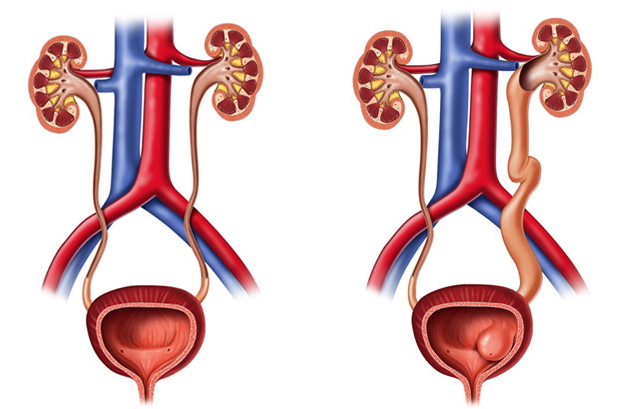

El ureterocele es malformación congenita consistente en la dilatación quística del uréter distal intravesical (dentro de la vejiga urinaria). Se atribuye a la ruptura retardada, o canalización incompleta, de la membrana de Chwalla, que divide al conducto de Wolf del seno urogenital en el momento de la formación de la yema ureteral durante el desarrollo embrionario, o a una deficiencia intrínseca del componente muscular del uréter distal. Puede asociarse a doble sistema colector. La disminución del calibre ureteral a su entrada en la vejiga, inferior al normal dificulta la entrada de orina en la misma, acumulándose en el ureter y provocando la dilatación.